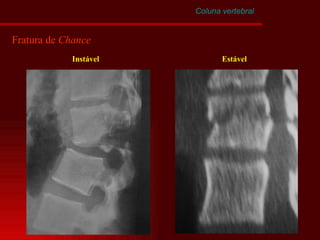

Coluna vertebral Fratura por Afastamento Tipos de fratura de  Chance Estável

Coluna vertebral Fratura de  Chance Instável Estável

Coluna vertebral Fraturas-Luxações Cisalhamento

Coluna vertebral Fraturas-Luxações Cisalhamento Acomete as três colunas Associadas a lesões neurológicas graves